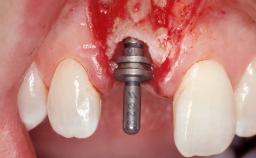

Immediate Flapless Placement of an Implant in a Maxillary Left Central Incisor Site

A 42-year-old female patient was referred to our clinic at the School of Dentistry of the University of São Paulo in November 2004, presenting a deficient restoration in the upper left central incisor. The clinical examination revealed no gingival retraction or any signs of gingival inflammation and, therefore, previous periodontal treatment was not considered. The patient presented a high lip line at full smile and a thin tissue biotype. This combination characterized a high-risk situation from an anatomic point of view, which required careful preoperative planning and cautious surgical execution.

| Placement Protocol | Immediate implant placement |

| Tooth Site | Maxillary incisor or canine |

| Socket Morphology | Single-root socket |

| Socket Integrity | Sufficient, with intact bone walls |